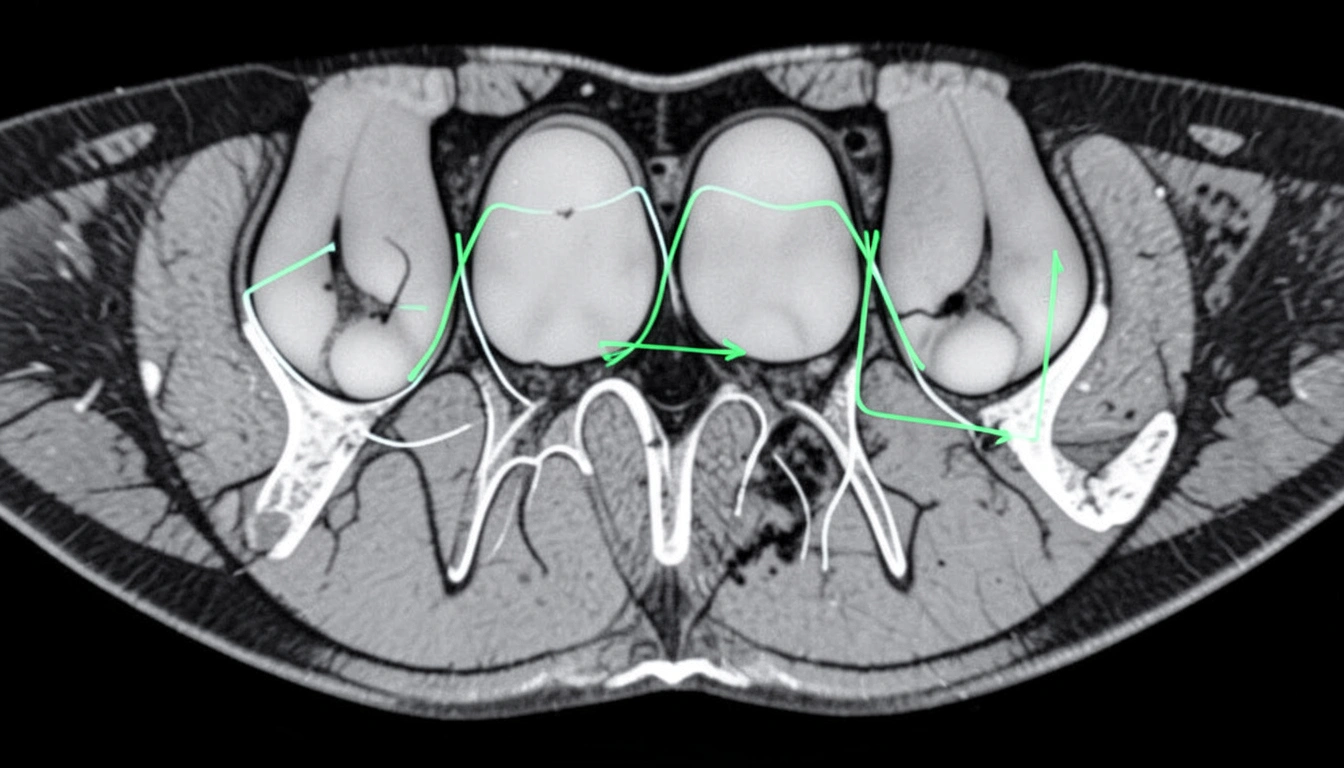

- 복잡한 해부학적 구조의 정밀 세그멘테이션: 임플란트 식립 시 가장 위험한 요소는 신경관 손상입니다. AI는 하치조 신경관, 이신경관, 상악동 경계 등을 정확히 분할하여 3차원 모델링에 반영합니다. 이는 수술 전에 위험 구역을 명확히 예측하여 수술 오차율을 최소화하는 데 핵심적인 역할을 합니다.

AI는 치아와 턱뼈 영역을 자동으로 분할(Segmentation)하고, 길이, 폭, 밀도를 측정합니다. 임플란트 식립을 고려할 때, AI는 식립 예정 부위의 잔존 뼈 높이(Residual Bone Height), 너비, 그리고 Hounsfield Unit(HU)로 표현되는 골 밀도를 자동으로 측정하여 즉각적인 보고서를 제공합니다. 특히 HU 값 분석은 뼈의 질을 객관적으로 평가할 수 있게 해, 수술 중 드릴링 전략이나 임플란트 종류 선택에 결정적인 기초 자료가 됩니다. AI가 제공하는 자동 측정 결과는 기존에 수동으로 측정하던 방식보다 빠르고 오차율이 낮습니다.

가장 혁신적인 부분은 진단 결과가 바로 치료 계획 시스템으로 연동된다는 점입니다. AI가 세그멘테이션한 해부학적 구조물(신경관, 턱뼈)을 기반으로, 임플란트 식립을 위한 3차원 수술 가이드 제작이 훨씬 정밀해집니다. AI는 최적의 식립 각도와 깊이를 제안하며, 수술 중 발생할 수 있는 잠재적인 위험 요소(인접 치아 손상, 신경관 침범 등)를 사전에 경고합니다. 이 시뮬레이션 기능을 통해 의료진은 환자에게 가장 안전하고 효율적인 수술 계획을 제시할 수 있으며, 환자 역시 자신의 수술 과정을 3차원 영상으로 이해할 수 있어 치료 동의율이 높아집니다.